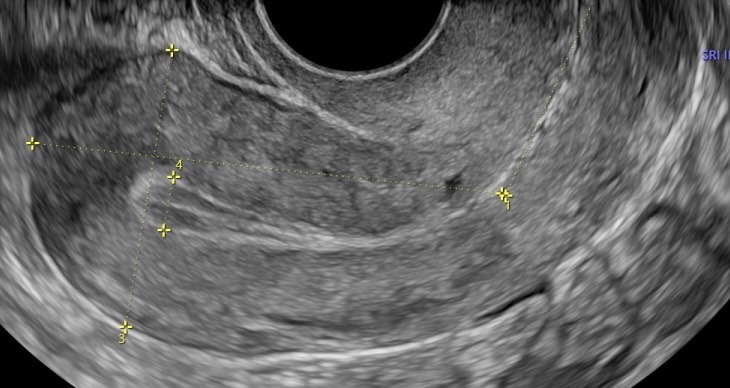

Histerosonografía

Procedimiento avanzado que utiliza ultrasonido y líquido para evaluar minuciosamente la cavidad uterina, ideal para descartar pólipos, miomas o anomalías.

Conteo Folicular

Evaluación ecográfica especializada para medir la reserva ovárica mediante el recuento de folículos antrales, fundamental en los estudios de fertilidad.